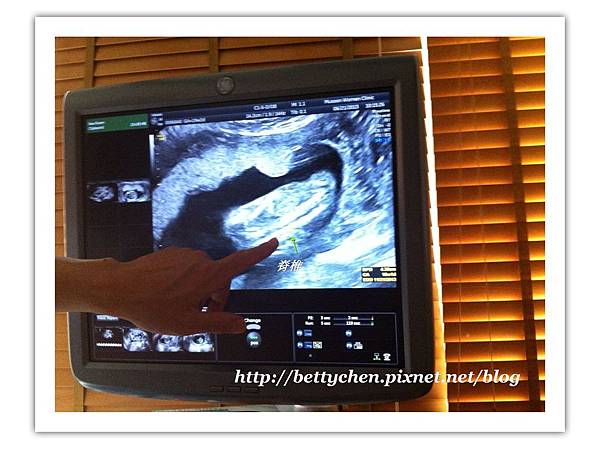

07

在他臉還沒轉過來前,先看看他的頭圍~

頭圍是量二耳間的距離,醫生說那個箭頭處是小腦!

08

這小子還是背對著我~~~來看看他的脊椎吧..很清楚!